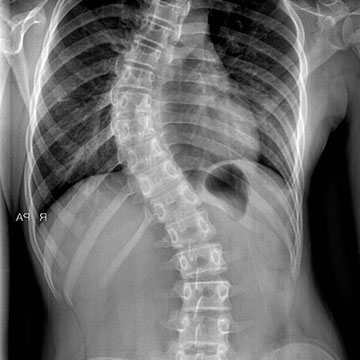

Scoliosis